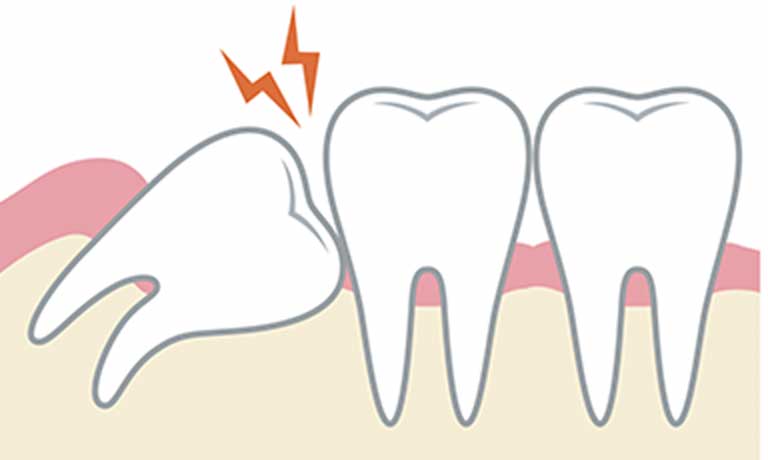

現代の人類は、顎の骨が小さくなった影響で、親知らずが生えてくるスペースが不足しがちになっています。そのため、他の歯と異なりまっすぐに生えてくることが少なく、多くは斜めに倒れて生えてきたり、まっすぐ生えてきても後ろ半分が歯ぐきで覆われたままになっていたりします。全く生えてこず、骨に埋まったままということも珍しくありません。

このようにきちんと生えてこない上に、最も奥にあるということで、歯磨きが非常に難しくなります。その結果、むし歯になりやすくなったり、化膿して腫れたりしやすくなります。